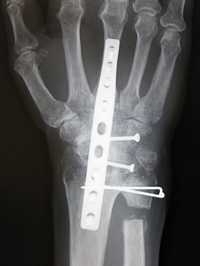

In this complete wrist fusion, the bones are held together with a combination of plates, screws, and pins.

In this total wrist replacement (arthroplasty), the worn-out bones have been replaced with an implant made of metal and plastic.